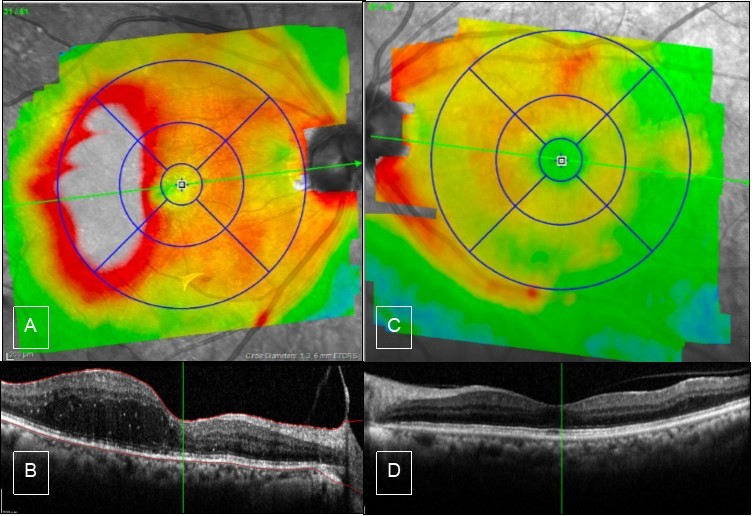

Figure 2.Case 1, OCT, OU. A & B) Right eye showed edema of the temporal macula involving fovea, there is PVD from the macula but still attached to the optic nerve. C & D) Left eye has partial PVD, otherwise it is unremarkable.

Figure 4.Case 2, OCT, OU. A) Right eye shows thickening of inferior macula. B) high definition scan shows epiretinal membrane which causes straightening of the foveal contour. C & D) Left eye OCT is unremarkable.